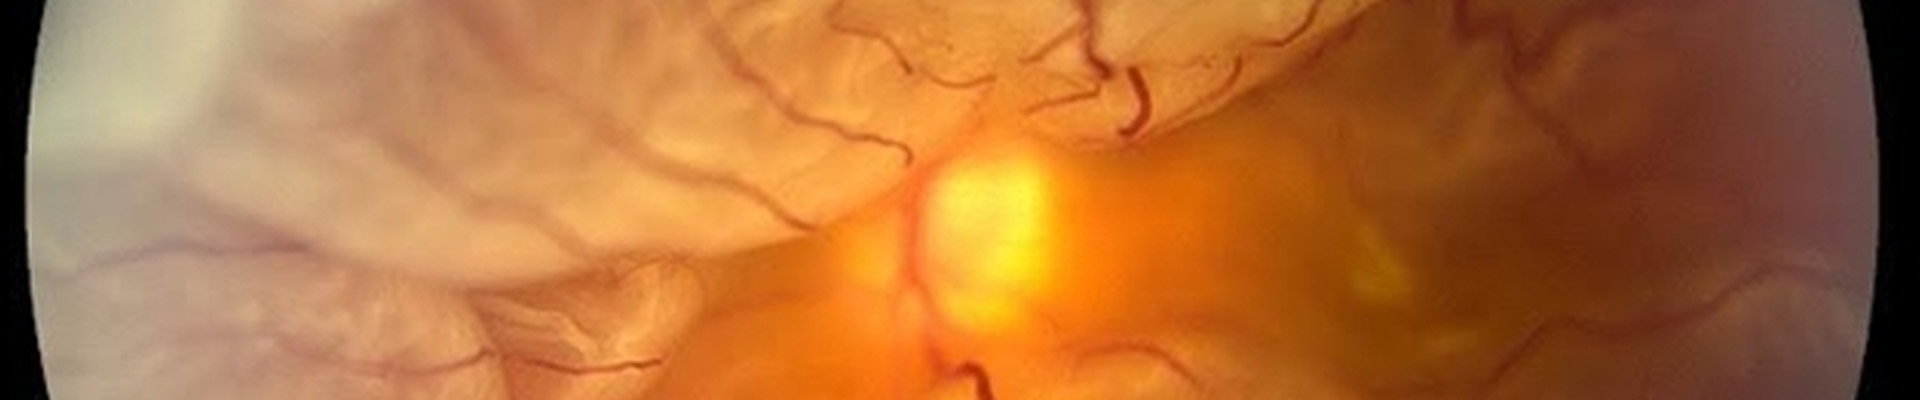

www.ophtalmique.chDécollement De Rétine | Institut De La Rétine | CHU De Nantes

www.ophtalmique.chDécollement De Rétine | Institut De La Rétine | CHU De Nantes